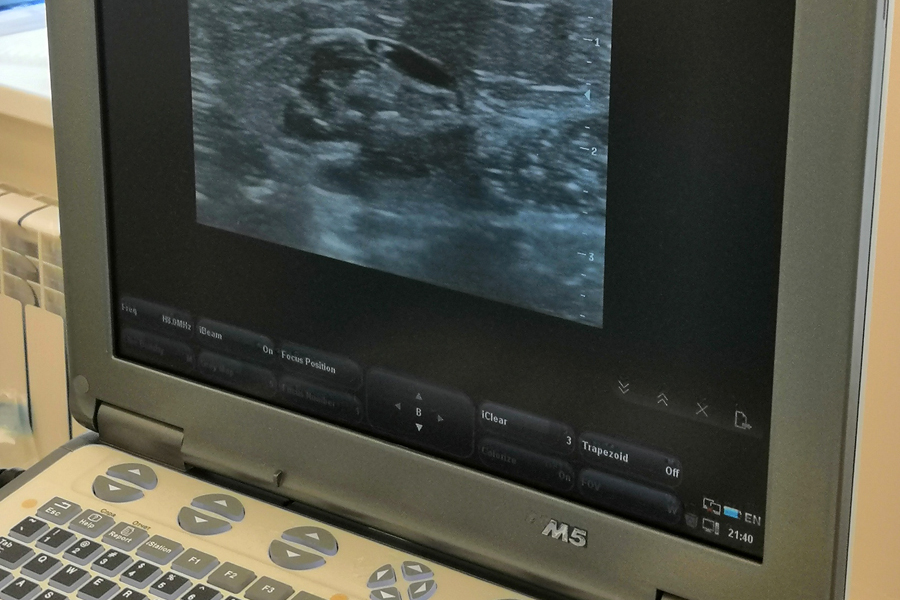

Операция проходит под контролем УЗИ, которое нужно для того, чтобы видеть лазерный световод в просвете вены. Обработанные вены через 2-3 месяца превращаются в соединительную ткань, а через полгода от них не остаётся и следа.